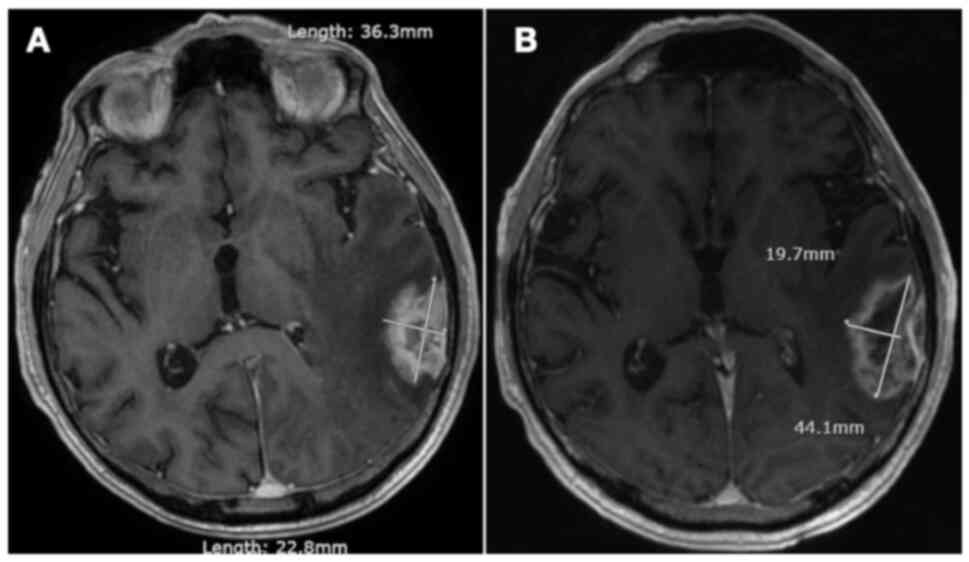

MRI of the head revealed 7 intracranial metastases within the left cerebral hemisphere, the largest of which measured 2 cm in diameter and was located in the left postcentral gyrus (Fig. 1A). Staging investigations demonstrated an 8.1 cm mass in the right apex of the lung with involvement of the chest wall and mediastinum, with no further distant metastases. Pathology from a CT-guided core biopsy of the lung mass revealed small cell carcinoma with positive immunohistochemical staining for synaptophysin, thyroid transcription factor 1, and cytokeratin AE1/AE3, with a perinuclear dot staining pattern. The malignant cells were negative for p63 and cytokeratin 5/6. Therefore, the patient was diagnosed with ES-SCLC.

Figure 1.

(A) Axial T1-weighted MRI of the head with contrast showing an enhancing mass in the superior medial aspect of the left postcentral gyrus. (B) Axial CT of the head with contrast showing no evidence of intracranial metastases following completion of whole brain radiotherapy and 6 cycles of chemotherapy.

In the context of numerous symptomatic brain metastases, palliative WBRT was delivered to a total dose of 20 Gy in 5 fractions. The patient then completed 6 cycles of palliative chemotherapy with cisplatin and etoposide. He endorsed overall improvement in his symptoms and functional abilities with treatment. Subsequent imaging showed interval reduction in the size of the right lung mass with no evidence of brain metastases on CT head (Fig. 1B). The patient then completed consolidative thoracic radiotherapy to a total dose of 30 Gy in 10 fractions. Regular follow-up imaging over the next 40 months revealed no evidence of disease progression in the thorax or CNS.

In mid-2019, approximately 3 years post-treatment, the patient began to notice a persistent, left-sided headache accompanied by short-term memory deficits. Physical examination demonstrated left-sided cerebellar dysfunction with nystagmus and clumsiness on heel-to-toe walking. Restaging investigations identified a new solitary mass measuring 3.6 cm with a broad dural base overlying the lateral left temporal and occipital lobe (Fig. 2A). No other evidence of intrathoracic or intraabdominal disease was appreciated. Neurosurgery was consulted but did not recommend surgical resection given the high risk of morbidity, particularly Wernicke's aphasia. The patient thus underwent stereotactic radiation to the solitary brain metastasis, 30 Gy in 5 fractions (Table SI). Follow-up MRI imaging demonstrated positive response to treatment with a gradual decrease in the size of the mass. However, there was also subsequent evidence of evolving radiation necrosis in the treated area, associated with mild memory loss and word-finding difficulties (Fig. 2B). As these symptoms were overall quite minor and improved spontaneously with time, no specific treatments for radionecrosis were implemented.

Figure 2.

(A) Axial T1-weighted MRI of the head with contrast showing a large mass with a broad dural base overlying the lateral left temporal and occipital lobe. (B) Axial T1-weighted MRI of the head with contrast showing an area of heterogenous enhancement within the left temporal lobe representing radionecrosis 8 months after completion of stereotactic radiation.